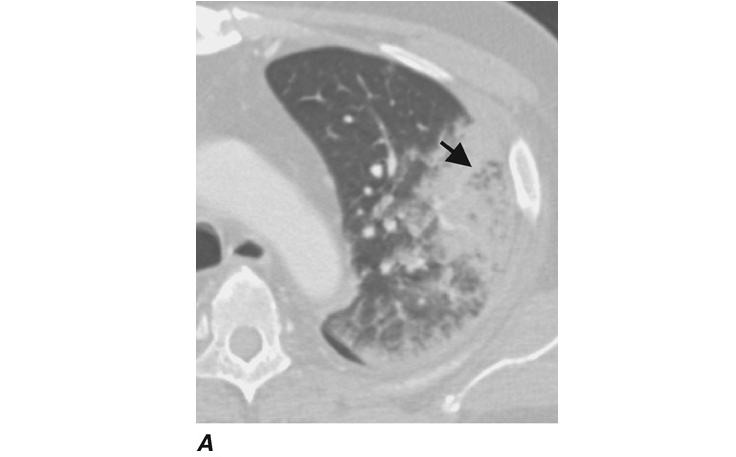

The diagnosis is usually based on presentation with a persistent chronic cough and sputum production accompanied by consistent radiographic features. While chest radiographs lack sensitivity, the presence of “tram tracks” indicating dilated airways is consistent with bronchiectasis. Chest CT is more specific for bronchiectasis and is the imaging modality of choice for confirming the diagnosis. CT findings include airway dilation (detected as parallel “tram tracks” or as the “signet-ring sign”—a cross-sectional area of the airway with a diameter at least 1.5 times that of the adjacent vessel), lack of bronchial tapering (including the presence of tubular structures within 1 cm from the pleural surface), bronchial wall thickening in dilated airways, inspissated secretions (e.g., the “tree-in-bud” pattern), or cysts emanating from the bronchial wall (especially pronounced in cystic bronchiectasis; Fig. I-1).